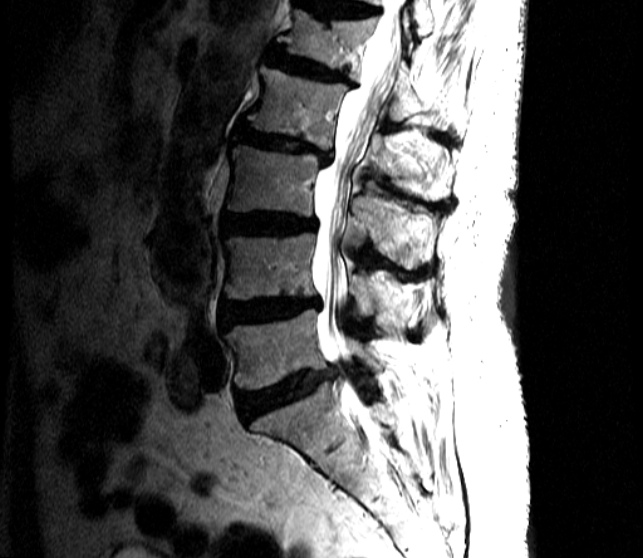

El área de menor resistencia del anillo fibroso es en la parte posterior, siendo el sitio más común en donde ocurren las hernias de disco. Formalmente la hernia de disco consiste en la salida parcial del núcleo pulposo a través del anillo fibroso.